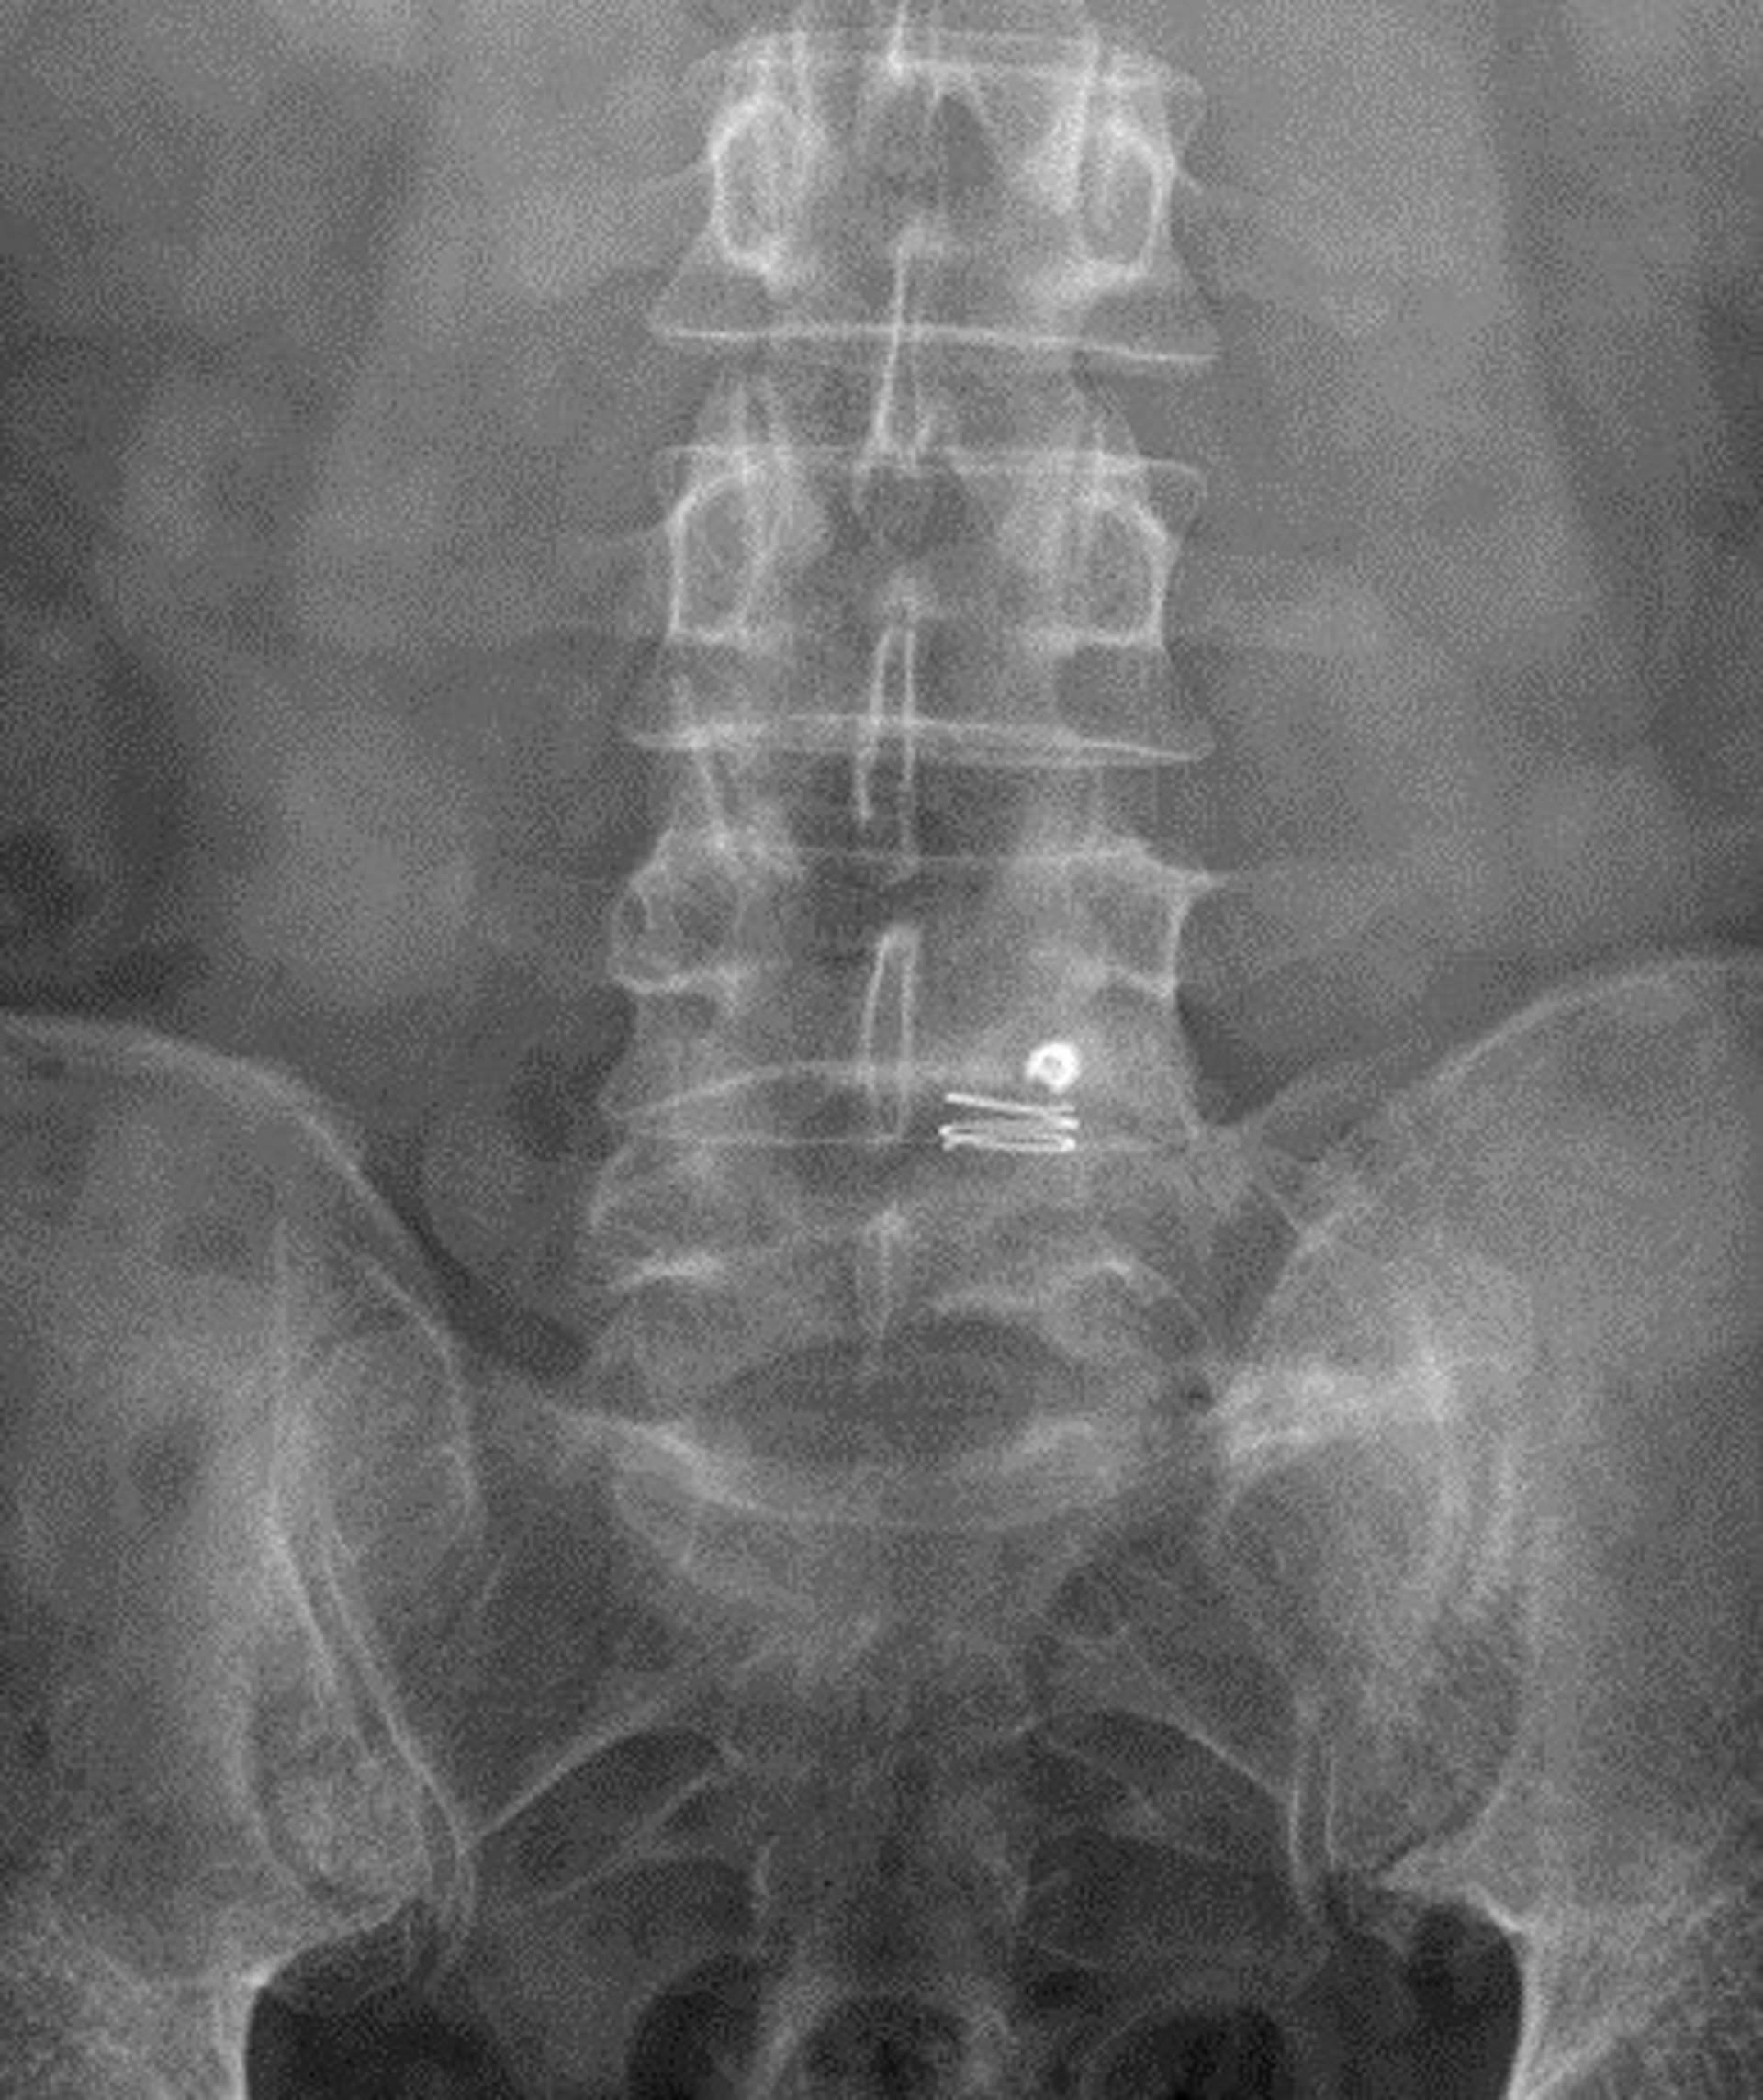

Dispositivo para prevenir la reaparición de las hernias discales lumbares.

Dispositivo para prevenir la reaparición de las hernias discales lumbares. - HOSPITAL DE BELLVITGE

Tras extirpar una hernia, el principal riesgo es que esta vuelva a aparecer o que se deteriore el disco de la columna, pero este sistema bloquea el anillo fibroso del disco invertebral sin interferir en los movimientos naturales de la columna, según ha informado el Hospital de Bellvitge este viernes en un comunicado.